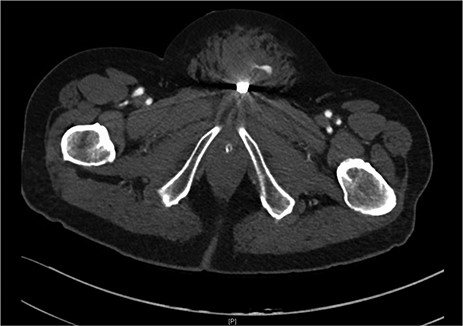

Suprapubic stab wound: coronal section: CT mesenteric angiogram showing mons pubis haematoma with active arterial extravasation.

After discussion with urology, a 14Fr indwelling catheter was inserted, which drained yellow urine. A computed tomography (CT) mesenteric angiogram demonstrated penetrating injury to the suprapubic region with haematoma and two foci of arterial extravasation with radiological evidence of peritoneal breach, and the metallic foreign body in situ (Figs 2 and 3). Importantly, the tip of the knife appeared to end at the base of the penis at the expected confluence of the dorsal vein.